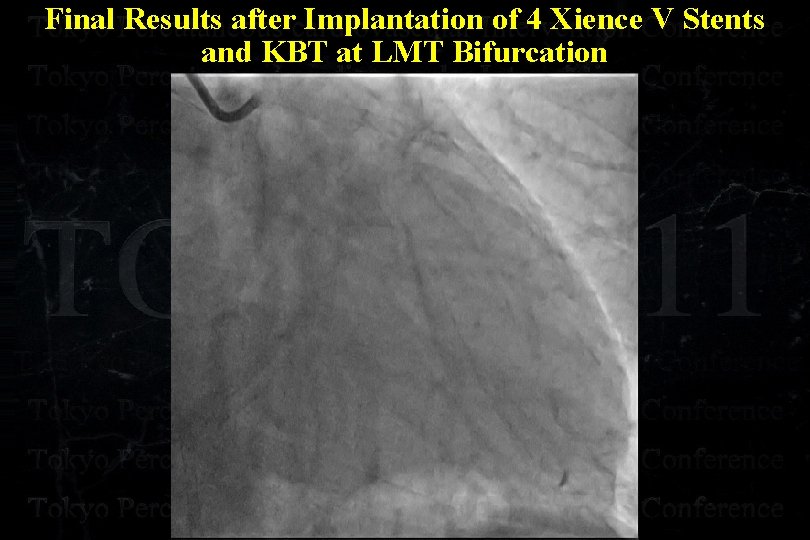

Final Results after Implantation of 4 Xience V Stents and KBT at LMT Bifurcation

Final Results after Implantation of 4 Xience V Stents and KBT at LMT Bifurcation

Final Results after Implantation of 4 Xience V Stents and KBT at LMT Bifurcation